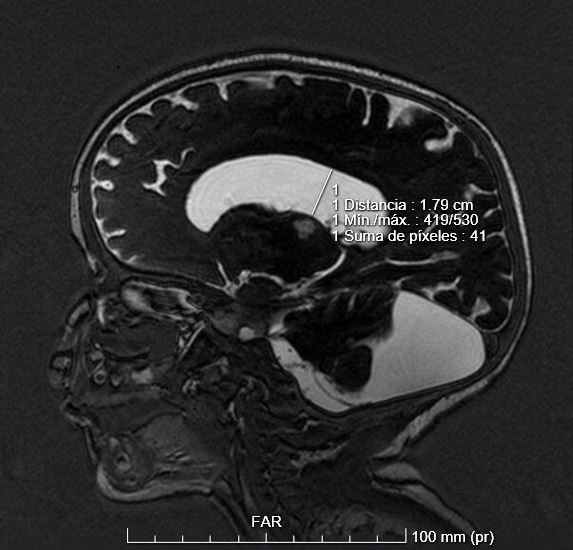

• RM cerebral compatible con malformación de Dandy-Walker sin cambios respecto a la previa.

• En cuanto a la valoración por Dermatología, se realiza estudio del pelo, observando la imagen que se muestra.